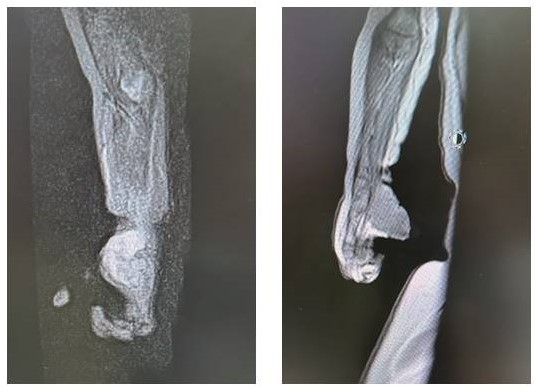

28.11.2022 выполнена МРТ кисти с внутривенным контрастированием. На ладонной поверхности правой кисти, распространяясь на область запястья, определяется однородной структуры новообразование размерами 3,0 × 3,5 × 3,0 см, интенсивно накапливающее контрастный препарат. Мягкие ткани вокруг новообразования утолщены. Мышца, отводящая мизинец, интимно прилежит к опухоли, граница нечеткая. Сухожилия поверхностного сгибателя, ладонный апоневроз без признаков инфильтрации. Магистральные сосуды интактны. Заключение: картина новообразования мягких тканей ладонной поверхности правой кисти (рисунок 2).

Рисунок 2

МРТ: на ладонной поверхности правой кисти, распространяясь на область запястья, определяется однородной структуры новообразование размерами 3,0 × 3,5 × 3,0 см, интенсивно накапливающее контрастный препарат

Figure 2

Magnetic resonance imaging: a neoplasm of homogeneous structure measuring 3.0 × 3.5 × 3.0 cm with intense contrast enhancement is observed оn the palmar surface of the right hand, extending to the wrist area